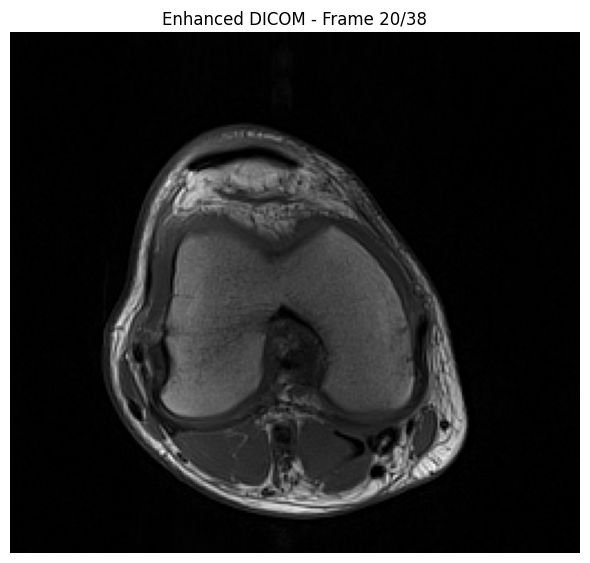

Decode Multi-Frame DICOM#

The pydicom plugin automatically handles multi-frame DICOM decoding:

# Decode the enhanced DICOM (directly from memory, no file needed)

print(f"Enhanced DICOM in memory")

print(f"Transfer Syntax: {enhanced_ds.file_meta.TransferSyntaxUID.name}")

num_frames = enhanced_ds.NumberOfFrames

print(f"Number of frames: {num_frames}")

# Decode all frames (GPU-accelerated)

start_time = time.time()

pixel_array = enhanced_ds.pixel_array

print(f"Pixel array shape: {pixel_array.shape}")

decode_time = time.time() - start_time

print(f"✓ Decoded in {decode_time:.3f}s ({decode_time/num_frames*1000:.2f} ms/frame)")

print(f"\nPixel array shape: {pixel_array.shape}")

print(f"Pixel array dtype: {pixel_array.dtype}")

# Display middle slice

middle_frame = pixel_array.shape[0] // 2

plt.figure(figsize=(6, 6))

plt.imshow(pixel_array[middle_frame], cmap="gray")

plt.title(f"Enhanced DICOM - Frame {middle_frame+1}/{num_frames}")

plt.axis('off')

plt.tight_layout()

plt.show()

Enhanced DICOM in memory

Transfer Syntax: High-Throughput JPEG 2000 with RPCL Options Image Compression (Lossless Only)

Number of frames: 38

Pixel array shape: (38, 234, 256)

✓ Decoded in 0.058s (1.54 ms/frame)

Pixel array dtype: uint16

../_images/samples_DICOM-transcoding_14_1.png